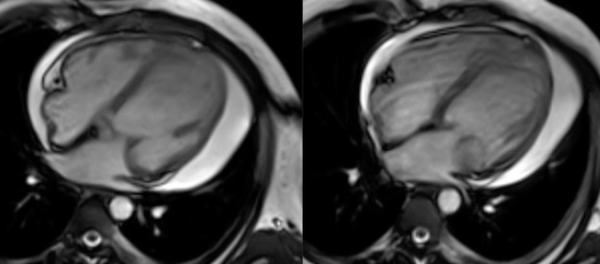

COD 158 - Septum Predominant HCM and RVoTo

RVoTo involvement in HCM is uncommon but diagnosing it may change the management plan and prognosis